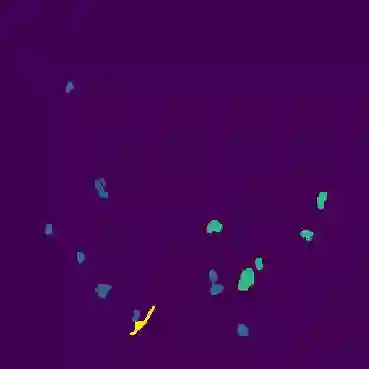

The novel coronavirus disease 2019 (COVID-19) has been spreading rapidly around the world and caused significant impact on the public health and economy. However, there is still lack of studies on effectively quantifying the lung infection caused by COVID-19. As a basic but challenging task of the diagnostic framework, segmentation plays a crucial role in accurate quantification of COVID-19 infection measured by computed tomography (CT) images. To this end, we proposed a novel deep learning algorithm for automated segmentation of multiple COVID-19 infection regions. Specifically, we use the Aggregated Residual Transformations to learn a robust and expressive feature representation and apply the soft attention mechanism to improve the capability of the model to distinguish a variety of symptoms of the COVID-19. With a public CT image dataset, we validate the efficacy of the proposed algorithm in comparison with other competing methods. Experimental results demonstrate the outstanding performance of our algorithm for automated segmentation of COVID-19 Chest CT images. Our study provides a promising deep leaning-based segmentation tool to lay a foundation to quantitative diagnosis of COVID-19 lung infection in CT images.

翻译:2019年新的冠状病毒疾病(COVID-19)在全世界迅速蔓延,对公共卫生和经济产生了重大影响;然而,对于有效量化COVID-19造成的肺感染,仍然缺乏研究;作为诊断框架的一项基本但具有挑战性的任务,分解在通过计算断层摄影(CT)图像测量的COVID-19感染的准确量化方面发挥着关键作用;为此,我们提出了对多个COVID-19感染区域进行自动分解的新型深层次学习算法。具体地说,我们利用综合残余变异学来学习一种稳健和直观的特征表征,并运用软关注机制来提高模型的能力,以区分COVID-19的症状。用公共CT图像数据集,我们验证了拟议的算法与其他相竞方法的功效。实验结果表明,我们自动分解COVID-19 Chest CT 图像的算法表现出色。我们的研究提供了一个充满希望的深度精细分解工具,为CT 图像中COVID-19肺感染的定量诊断奠定了基础。